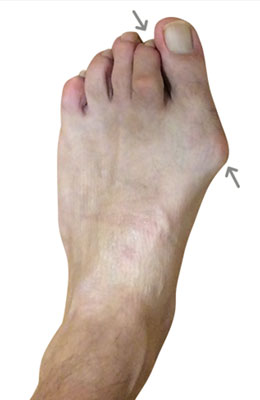

Lapidus Forever Bunionectomy™ and Hammertoe Correction

George is a 62-year-old businessman who presented with a sore on his second toe from rubbing on his shoes. We decided to correct his foot as a whole and performed several orthopedic surgical procedures as she had both types of bunions. He chose our Lapidus Forever Bunionectomy™, a hammertoe correction and an osteotomy for his Tailor’s Bunion (bunionette). George was weight bearing on his foot at two weeks and back in regular shoes at 8 weeks with no pain and full function.